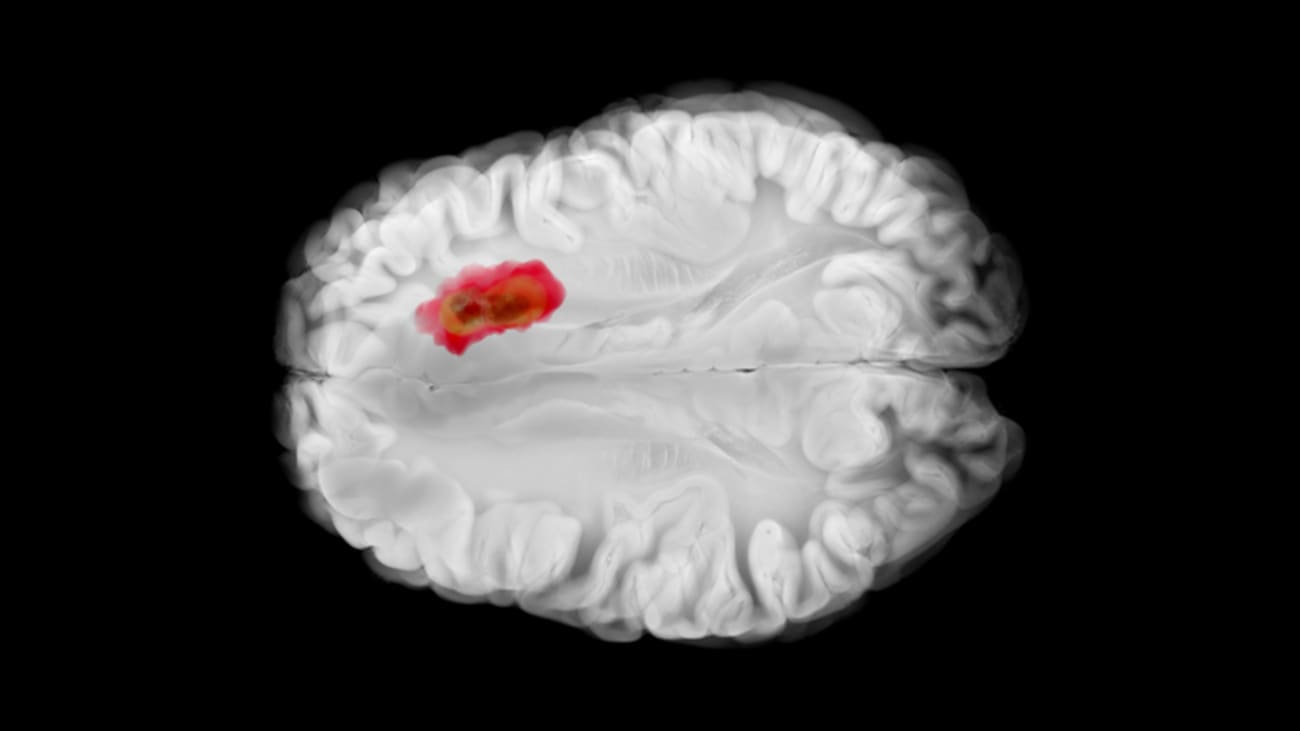

Glioma surgery in eloquent brain regions remains one of the greatest challenges in neurosurgery, demanding a balance between oncologic control and preservation of function. A recent study led by Evan Bander, M.D., Director of Endoscopic Skull Base Surgery and Co-Director of the Pituitary Tumor Program at Baptist Health Miami Neuroscience Institute, offers important new insights into how tumor location, extension, and surgical approach influence early neurocognitive outcomes after awake insular glioma resection. Beyond the publication itself, the work underscores the sophisticated array of techniques now being used at Baptist Health to maximize safety and precision in surgery for complex brain tumors.

The study examined 53 patients with insular gliomas who underwent awake craniotomy, most through a transsylvian approach and the remainder through a transcortical corridor. Neuropsychological testing before and after surgery revealed that early declines in memory and verbal fluency were common, highlighting the vulnerability of insular networks. While the overall difference between approaches was modest, patients undergoing transcortical surgery were significantly more likely to experience deterioration in verbal fluency. Tumor extension and location within the insula also mattered: left-hemisphere tumors were linked to greater declines in about half of the tested domains, lesions extending beyond the insula carried higher risk for fluency decline, and anterior or inferior quadrant tumors showed domain-specific vulnerabilities in executive function and recognition memory.